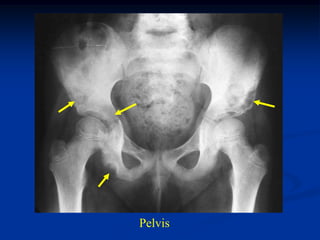

Case # 446

6 year female with HSC disease skull, spine and pelvis

Pelvis